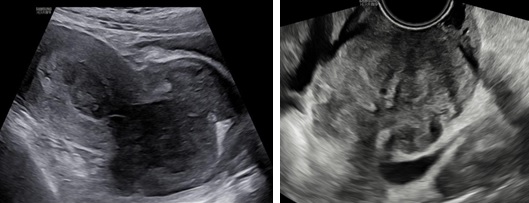

Siêu âm: Tử cung ngã trước, kích thước: 56 x 62 x 90 mm. Cơ tử cung mật độ đều, đồng nhất. Từ thành trước đoạn thân nhô vào lòng tử cung kéo dài tới cổ tử cung có khối echo dày không đồng nhất kích thước 64 x 81 x 70 mm, không rõ ranh giới với cổ tử cung và cơ tử cung. Trên Doppler màu khối tổn thương phần ở lòng tăng sinh mạch máu độ 2 và ở vùng cổ tử cung độ 4.

Hình 1: Hình siêu âm 2D ngã bụng (trái) và ngã âm đạo (phải) cho thấy tổn thương từ lòng tử cung lan tới cổ tử cung, không thấy ranh giới của khối này với cơ vùng cổ tử cung